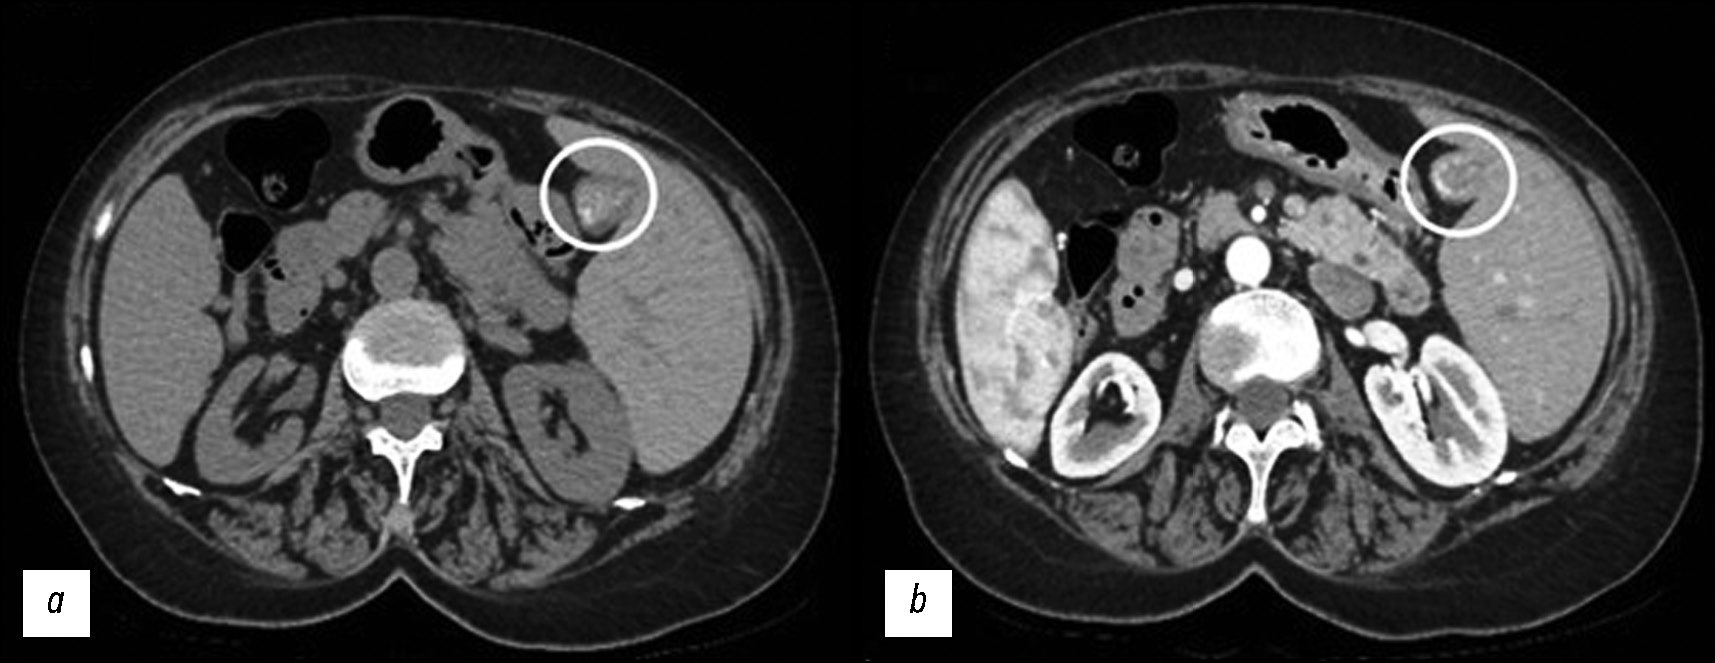

SI refers to a reversal positioning of the heart and major internal organs [1-4]. It is an uncommon congenital anomaly that manifests as a mirror-image transposition of both the abdominal and thoracic organs [5]. Dextrocardia (true mirror-image) is commonly related to SI, and the aorta is up-directed on the opposite side (Fig. 6).

Fig. 6. A series of VR images of the mediastinum that show the heart and aorta directed on the right from different perspectives (a in front) (b behind, on the left) (c behind, on the right) on rotation.

This condition could affect the chest, particularly the heart and large blood vessels because each cardiac chamber is asymmetrical; situs also applies to the heart. In addition, the anatomy of the arteries and the abdomen is mirrored (Fig. 7).

Fig. 7. The artery’s anatomy of the abdomen in the case of SIT: on the left, there is the liver, and the spleen is on the opposite side. The first is an angio-map (a) while the second is a VR image (b).